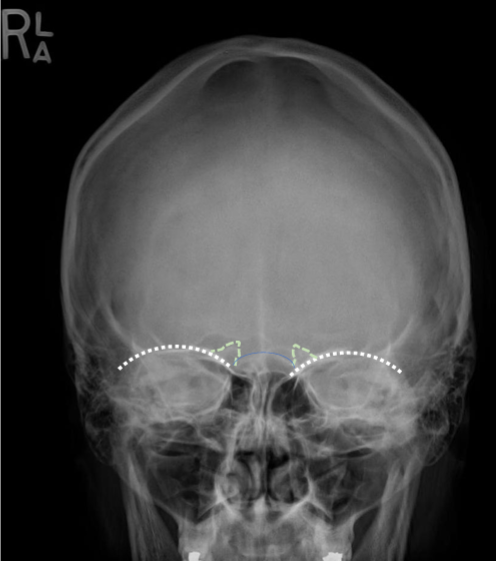

Critique - PA Axial (Caldwell)

MAIN Goal, F/E: petrous pyramids are projected into the lower 1/3 of the orbits

Tilt: supraorbital rims transversely aligned

Rotation: lateral border of the orbits equidistant to the lateral border of the cranium (rotation is towards the narrowed side)